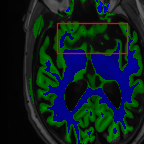

Sparsity LI 2D CNN 3D CNN Ours GT

4 Refer to caption (a) 0.6787/0.7972 Refer to caption (b) 0.8143/0.8776 Refer to caption (c) 0.8190/0.8714 Refer to caption (d) 0.8664/0.9085 Refer to caption (e) GM/WM

Refer to caption (f) 0.6808/0.7161 Refer to caption (g) 0.8103/0.8631 Refer to caption (h) 0.7950/0.8606 Refer to caption (i) 0.8598/0.9115 Refer to caption (j) GM/WM

8 Refer to caption (k) 0.5139/0.7240 Refer to caption (l) 0.6619/0.8224 Refer to caption (m) 0.6878/0.8584 Refer to caption (n) 0.7798/0.8853 Refer to caption (o) GM/WM

Refer to caption (p) 0.5910/0.6947 Refer to caption (q) 0.6516/0.8021 Refer to caption (r) 0.6507/0.8186 Refer to caption (s) 0.7471/0.8540 Refer to caption (t) GM/WM

Figure 6: Visual comparison of gray matter (Green)/white matter (Blue) segmentation over different methods, with respective DICE scores listed under the images.

In Fig. 6, we demonstrate the advantage of the proposed method in brain matter segmentation. It is clear that although 2D and 3D CNN generates visually plausible interpolation as presented in Fig. 5, the brain matters are easily misclassified due to incorrect anatomical structures and blurred details.